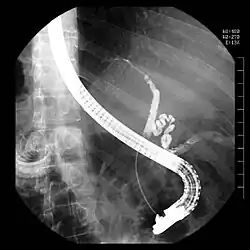

Bij een ERCP wordt een endoscoop door de mond van de patiënt naar binnen gebracht. Dit is een lange slang met glasvezel en aan het uiteinde een lens. Aan het andere uiteinde kan een videocamera worden bevestigd. Door de endoscoop kunnen verschillende instrumenten worden ingebracht. De endoscoop passeert de maag en komt dan in de twaalfvingerige darm. Daar bevindt zich de uitmonding van de galgang, die de papil van Vater wordt genoemd. Instrumenten kunnen worden opgevoerd in de papil van Vater. Als er dan contrastvloeistof in de galgang wordt gespoten, kunnen er röntgenfoto's worden gemaakt die de galgang afbeelden.

Afwijkingen die met een ERCP kunnen worden vastgesteld zijn galstenen in de galgang, een pancreaskopcarcinoom[1] of andere aandoeningen van de galgang, maar er kunnen met een ERCP ook interventies worden uitgevoerd, zoals het verwijderen van galstenen uit de galgang of het plaatsen van een stent in de galgang. Een stent is een plastic of metalen buisje dat wordt ingebracht in de galgang als die vernauwd is en is ervoor om te zorgen dat de gal naar de darm kan blijven afvloeien. Een ERCP wordt meestal door een gastro-enteroloog uitgevoerd.